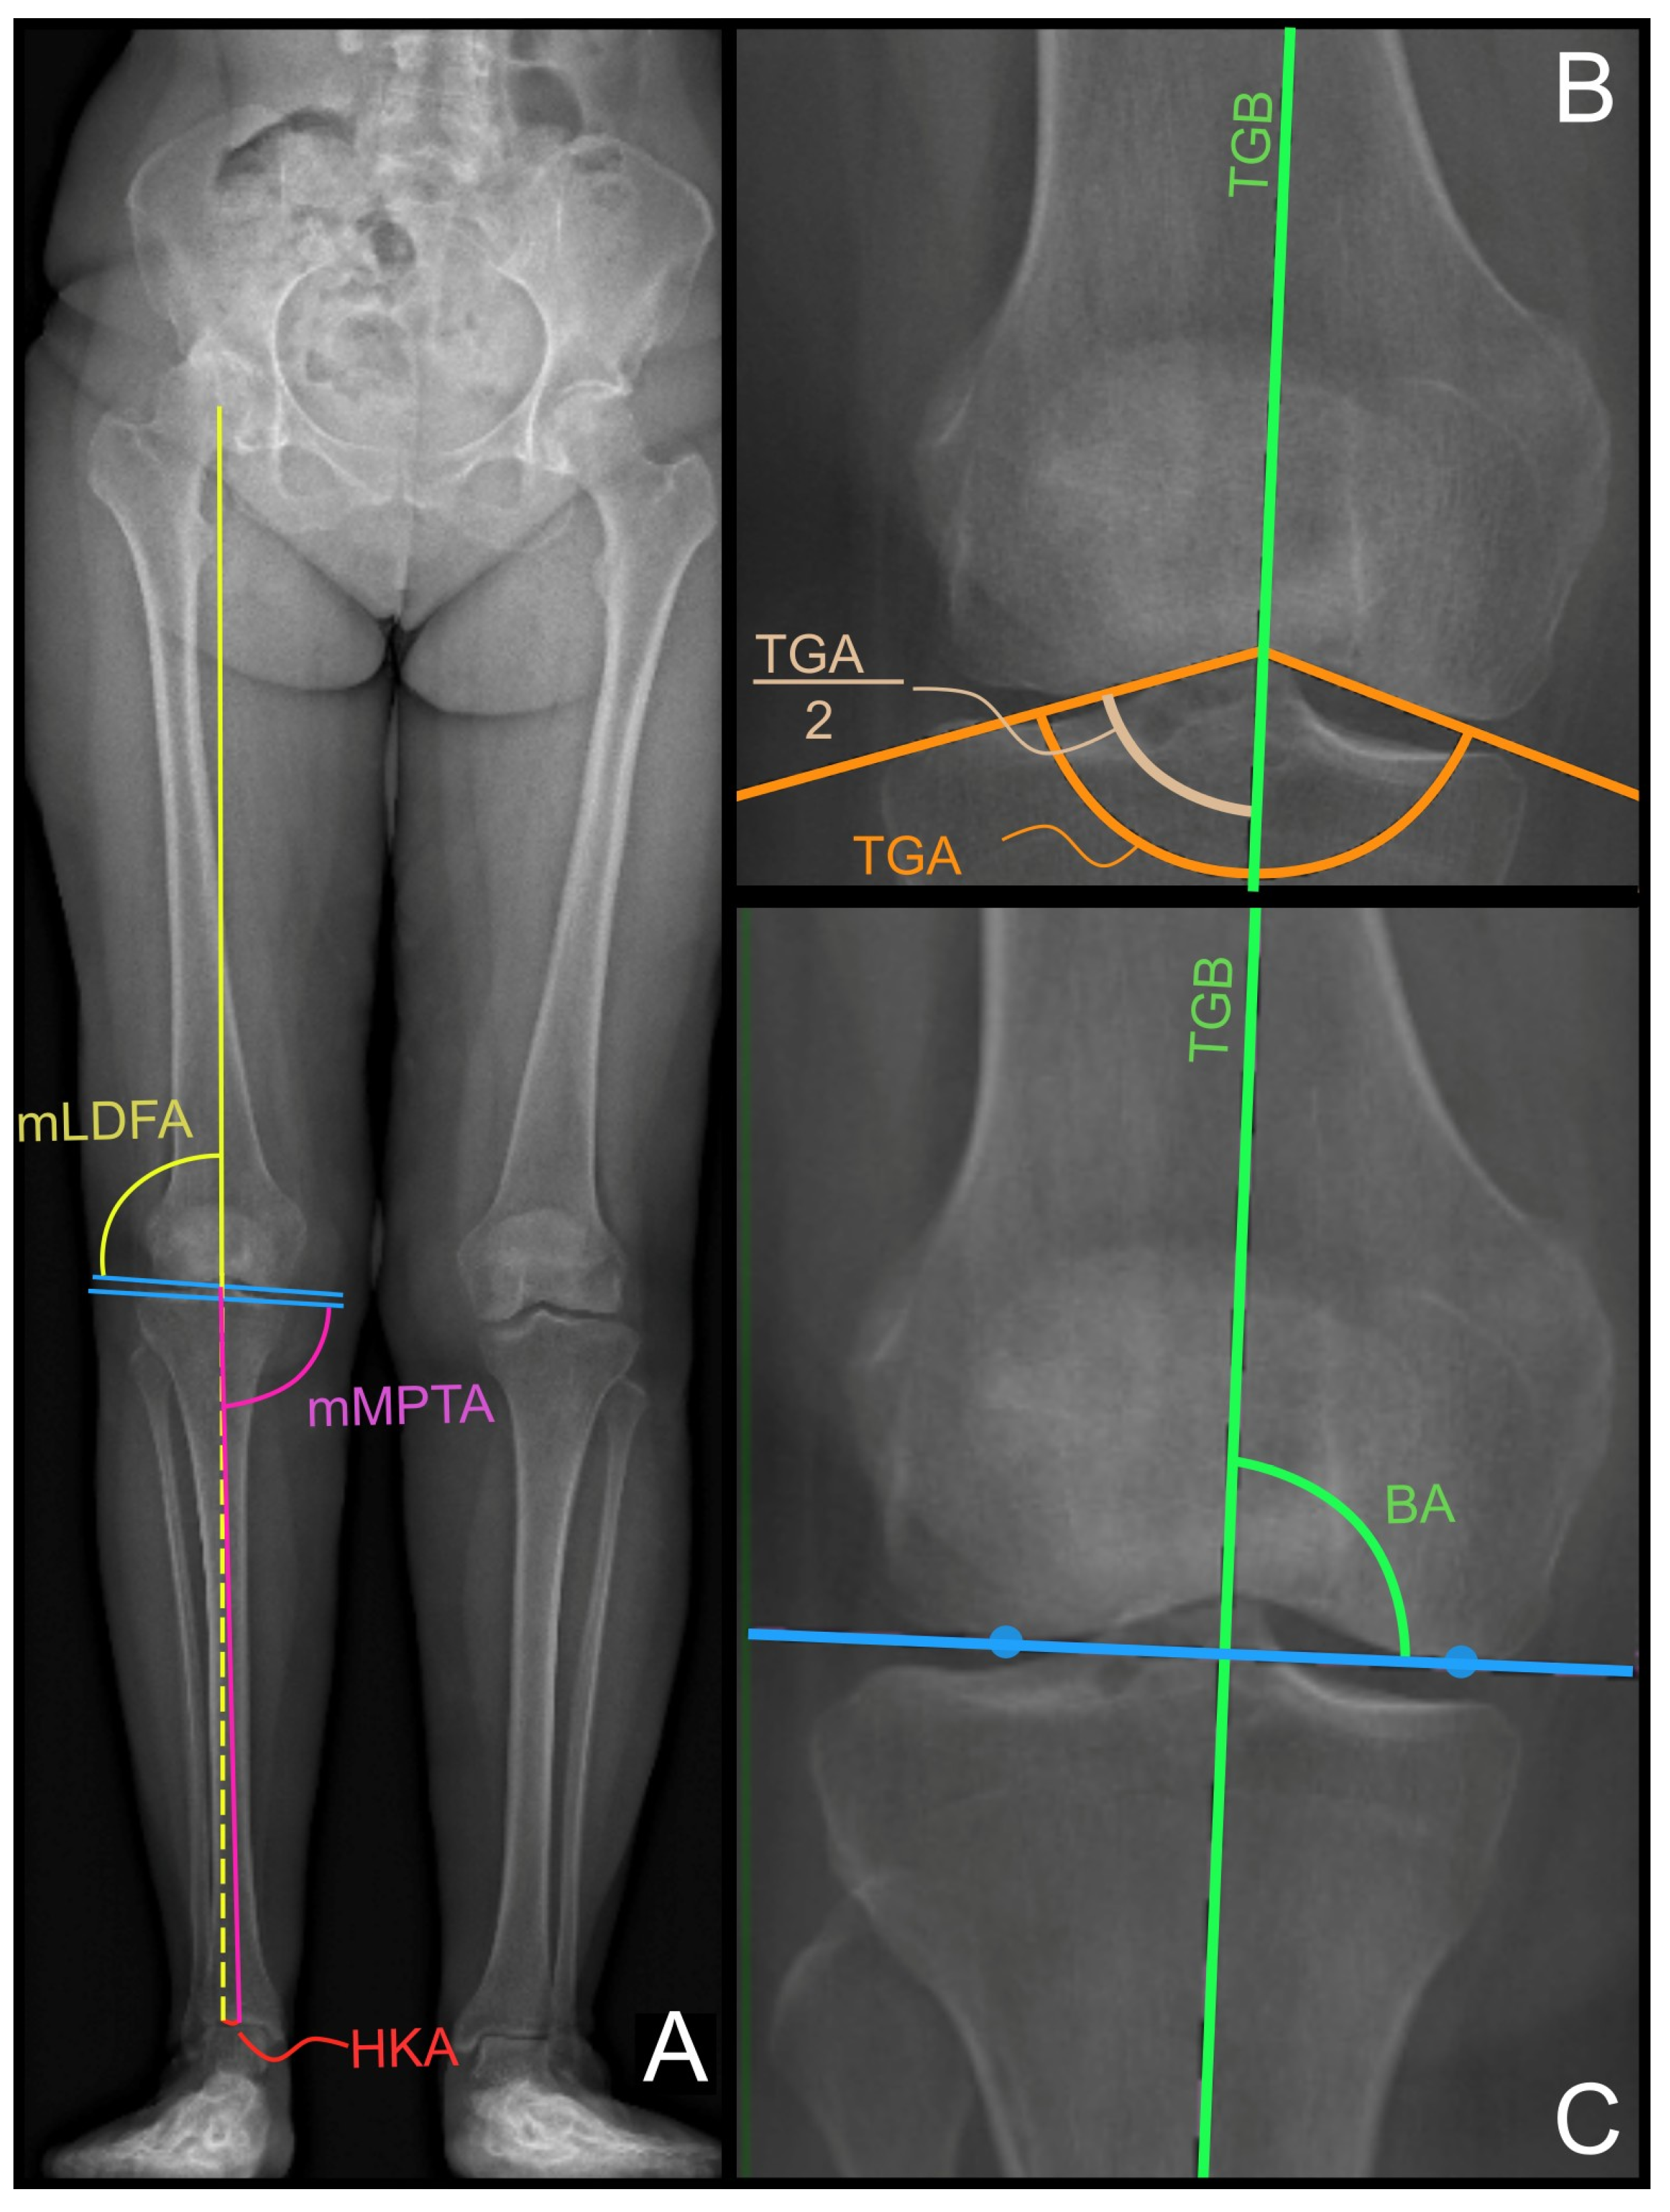

- Two lines are drawn tangentially to the medial and later aspects of the trochlear groove, starting from the radiographic apical midpoint of the inter-condylar groove. The trochlear groove angle (TGA) is measured as an angle subtended by these two lines (see Figure 1B, orange lines);

- The TGB is drawn as the line that bisects the TGA and passes through the radiographic apical midpoint of the inter-condylar groove (see Figure 1B, green line);

- The bisector angle (BA) is measured as the medial angle between the TGB and the distal femur joint line, which is defined as the line passing through the two most prominent points of the medial and lateral condyles (refer to Figure 1C, respectively, the green angle, blue line, and blue dots).